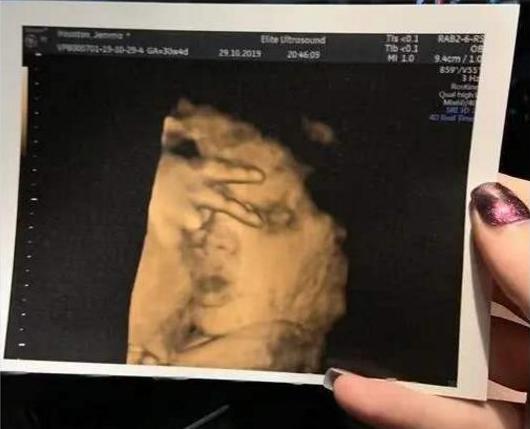

1. 镜头感十足的比耶照

要说孩子的镜头感还真的是娘胎里带的,别说你不信,这个宝妈就分享了自己最珍贵的一张B超照片,因为这张照片可以说是要不是亲眼所见,谁都不敢相信这是一个小胎儿自发有的镜头感,这也是宝妈去做产检,然后再拍B超的时候宝宝就超级配合。

在医生确认完胎儿的身体发育没有什么问题的时候,准备给宝妈拍一张B超照片拿回去,结果就在这个时候宝宝突然就举起小手正好放在眼睛周围,还比了一个耶,这让当时所有在场的人都愣住了,不得不说妈妈爱拍照这一点还真是从小就会遗传给宝宝。